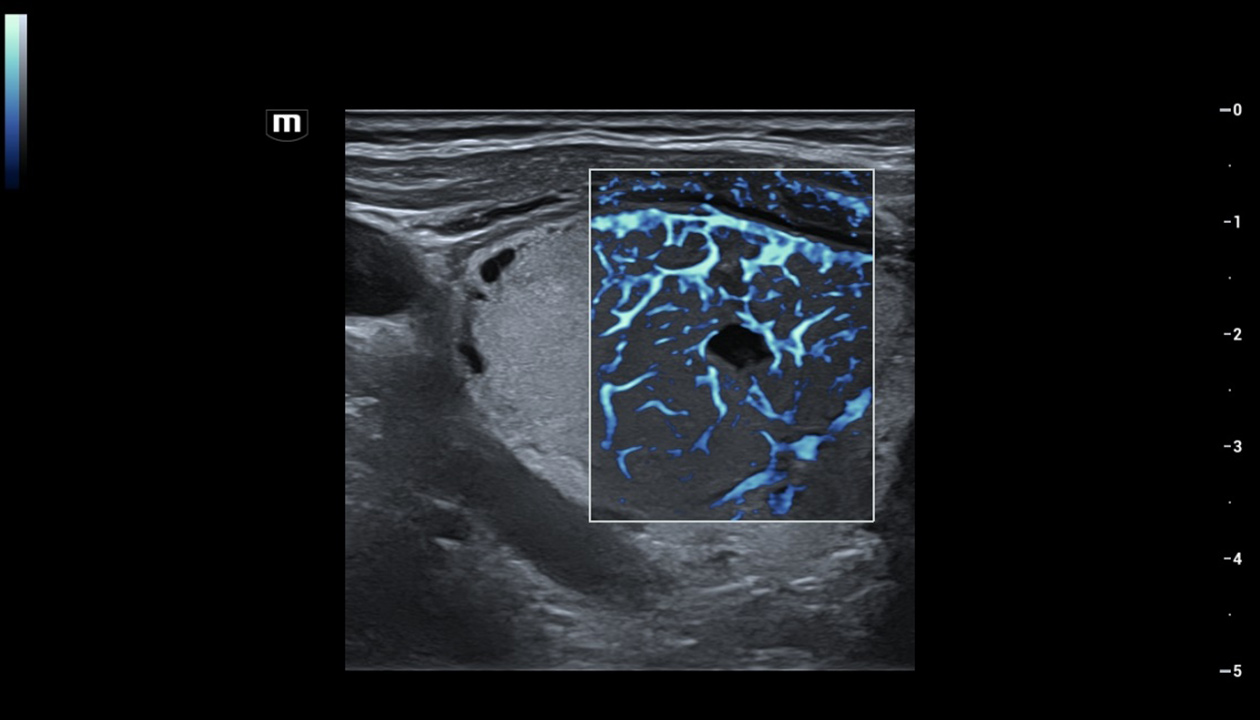

Powered by ZST +

The ZST + platform represents an extraordinary leap forward in ultrasound technology, moving away from traditional beam-forming to channel data processing. This groundbreaking innovation overcomes the traditional trade-offs among spatial resolution, temporal resolution, and tissue uniformity, resulting in unparalleled image quality that empowers infinite imaging solutions.

Resona I9 provides comprehensive clinical solutions for dedicated applications. Based on in-depth insights into different clinical scenarios, it delivers innovations that give users extreme clarity, outstanding intelligence and enhanced diagnostic confidence.